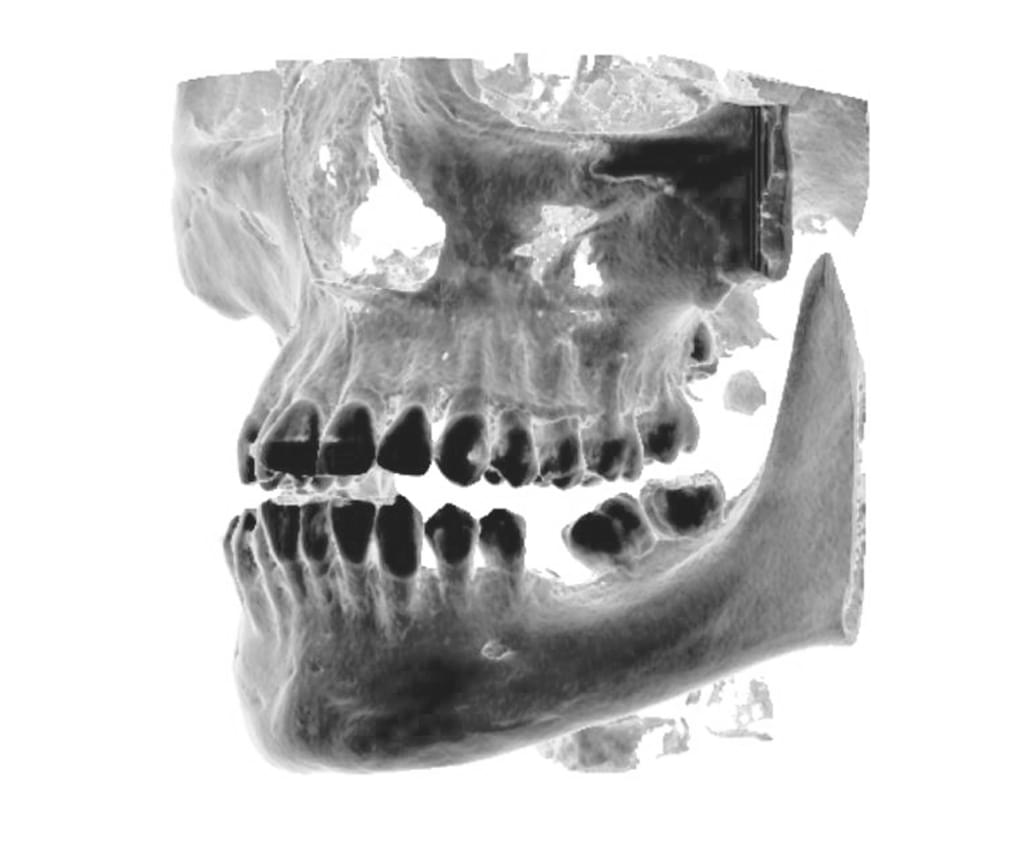

Výpočetní tomografie

(3d čelisťové snímky a snímky ústní dutiny)

CBCT Maxilofaciální diagnostika